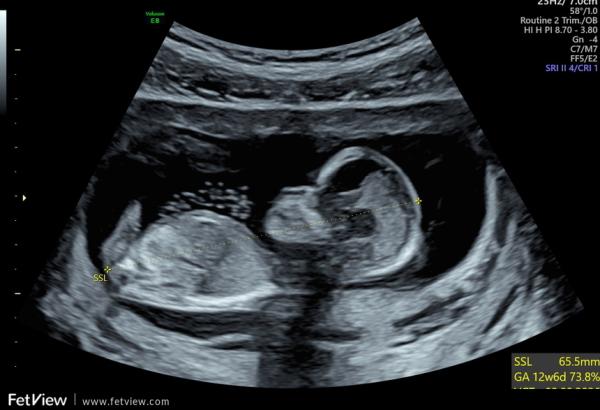

Guten Morgen,  ich bin derzeit in der 13. SSW und hatte letzte Woche einen Ultraschall. Was meint ihr, kann man das Geschlecht erkennen?  Der Arzt hatte eine klare Tendenz die er uns leider bisher nicht mitgeteilt hat.  Ich kann leider nichts wirklich erkennen.  Hier die Bilder aus 12+3. Vielen Dank fürs Miträtseln.